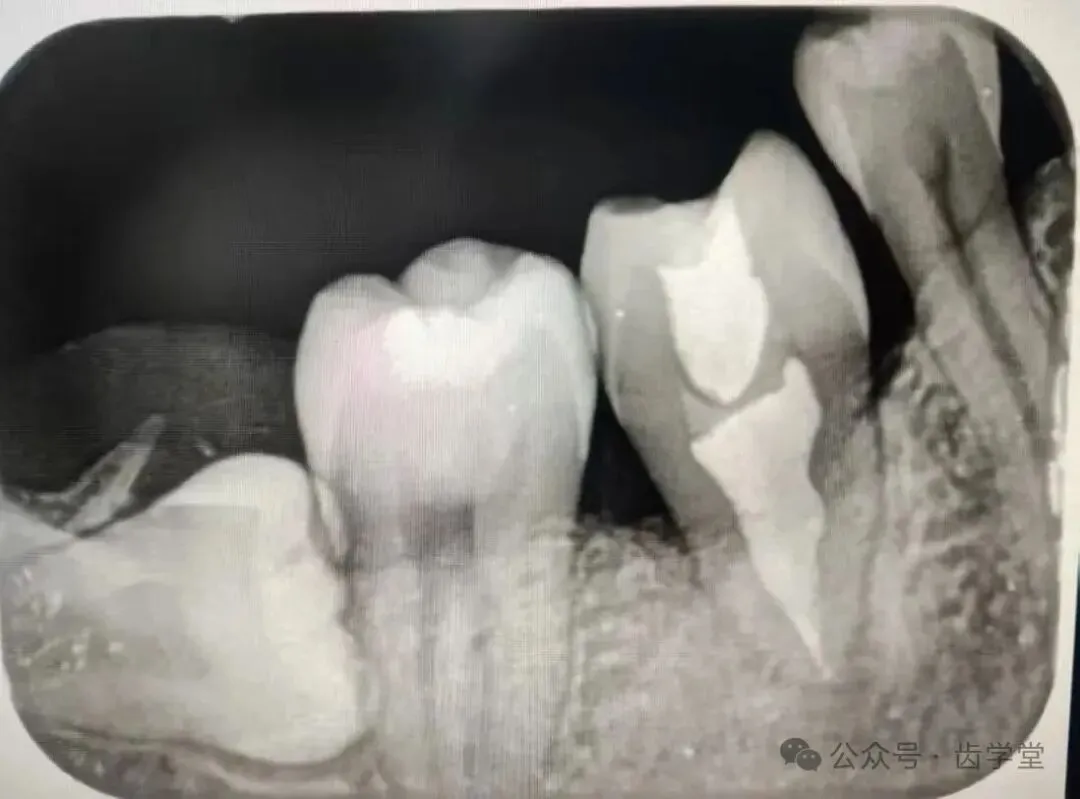

12.供牙微创拔除的操作要点详解;

13.受植位点不同情况移植的区别及其要点;

15.自体牙移植术中初期稳定性的重要性和方法;

17.牙周膜保护在自体牙移植的重要性;

1.供牙八字法微创拔除技巧,牙周膜保护的方法及疑难复杂供牙术前处理方法(术前正畸类);

2.受植区患牙拔除方法,受植窝精准预备方法;